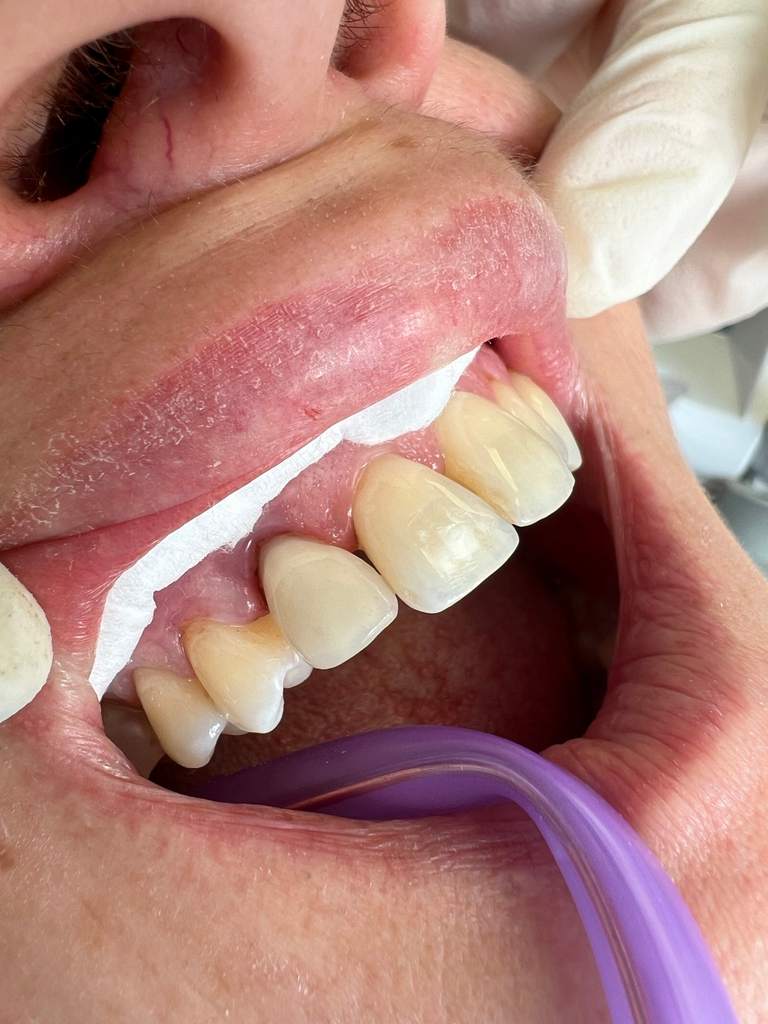

Στο ιατρείο ακολουθείται το νεότερο και πλέον σύγχρονο πρωτόκολλο θεραπείας (GBTguidedbiofilmtherapy), σύμφωνα με το οποίο ο οδοντιατρικός καθαρισμός, η θεραπεία ουλίτιδας και η περιοδοντική θεραπεία στη φάση ελέγχου της φλεγμονής και διατήρησης του αποτελέσματός της, πραγματοποιούνται με το πιο αποτελεσματικό, ήπιο και ελάχιστα επεμβατικό τρόπο.